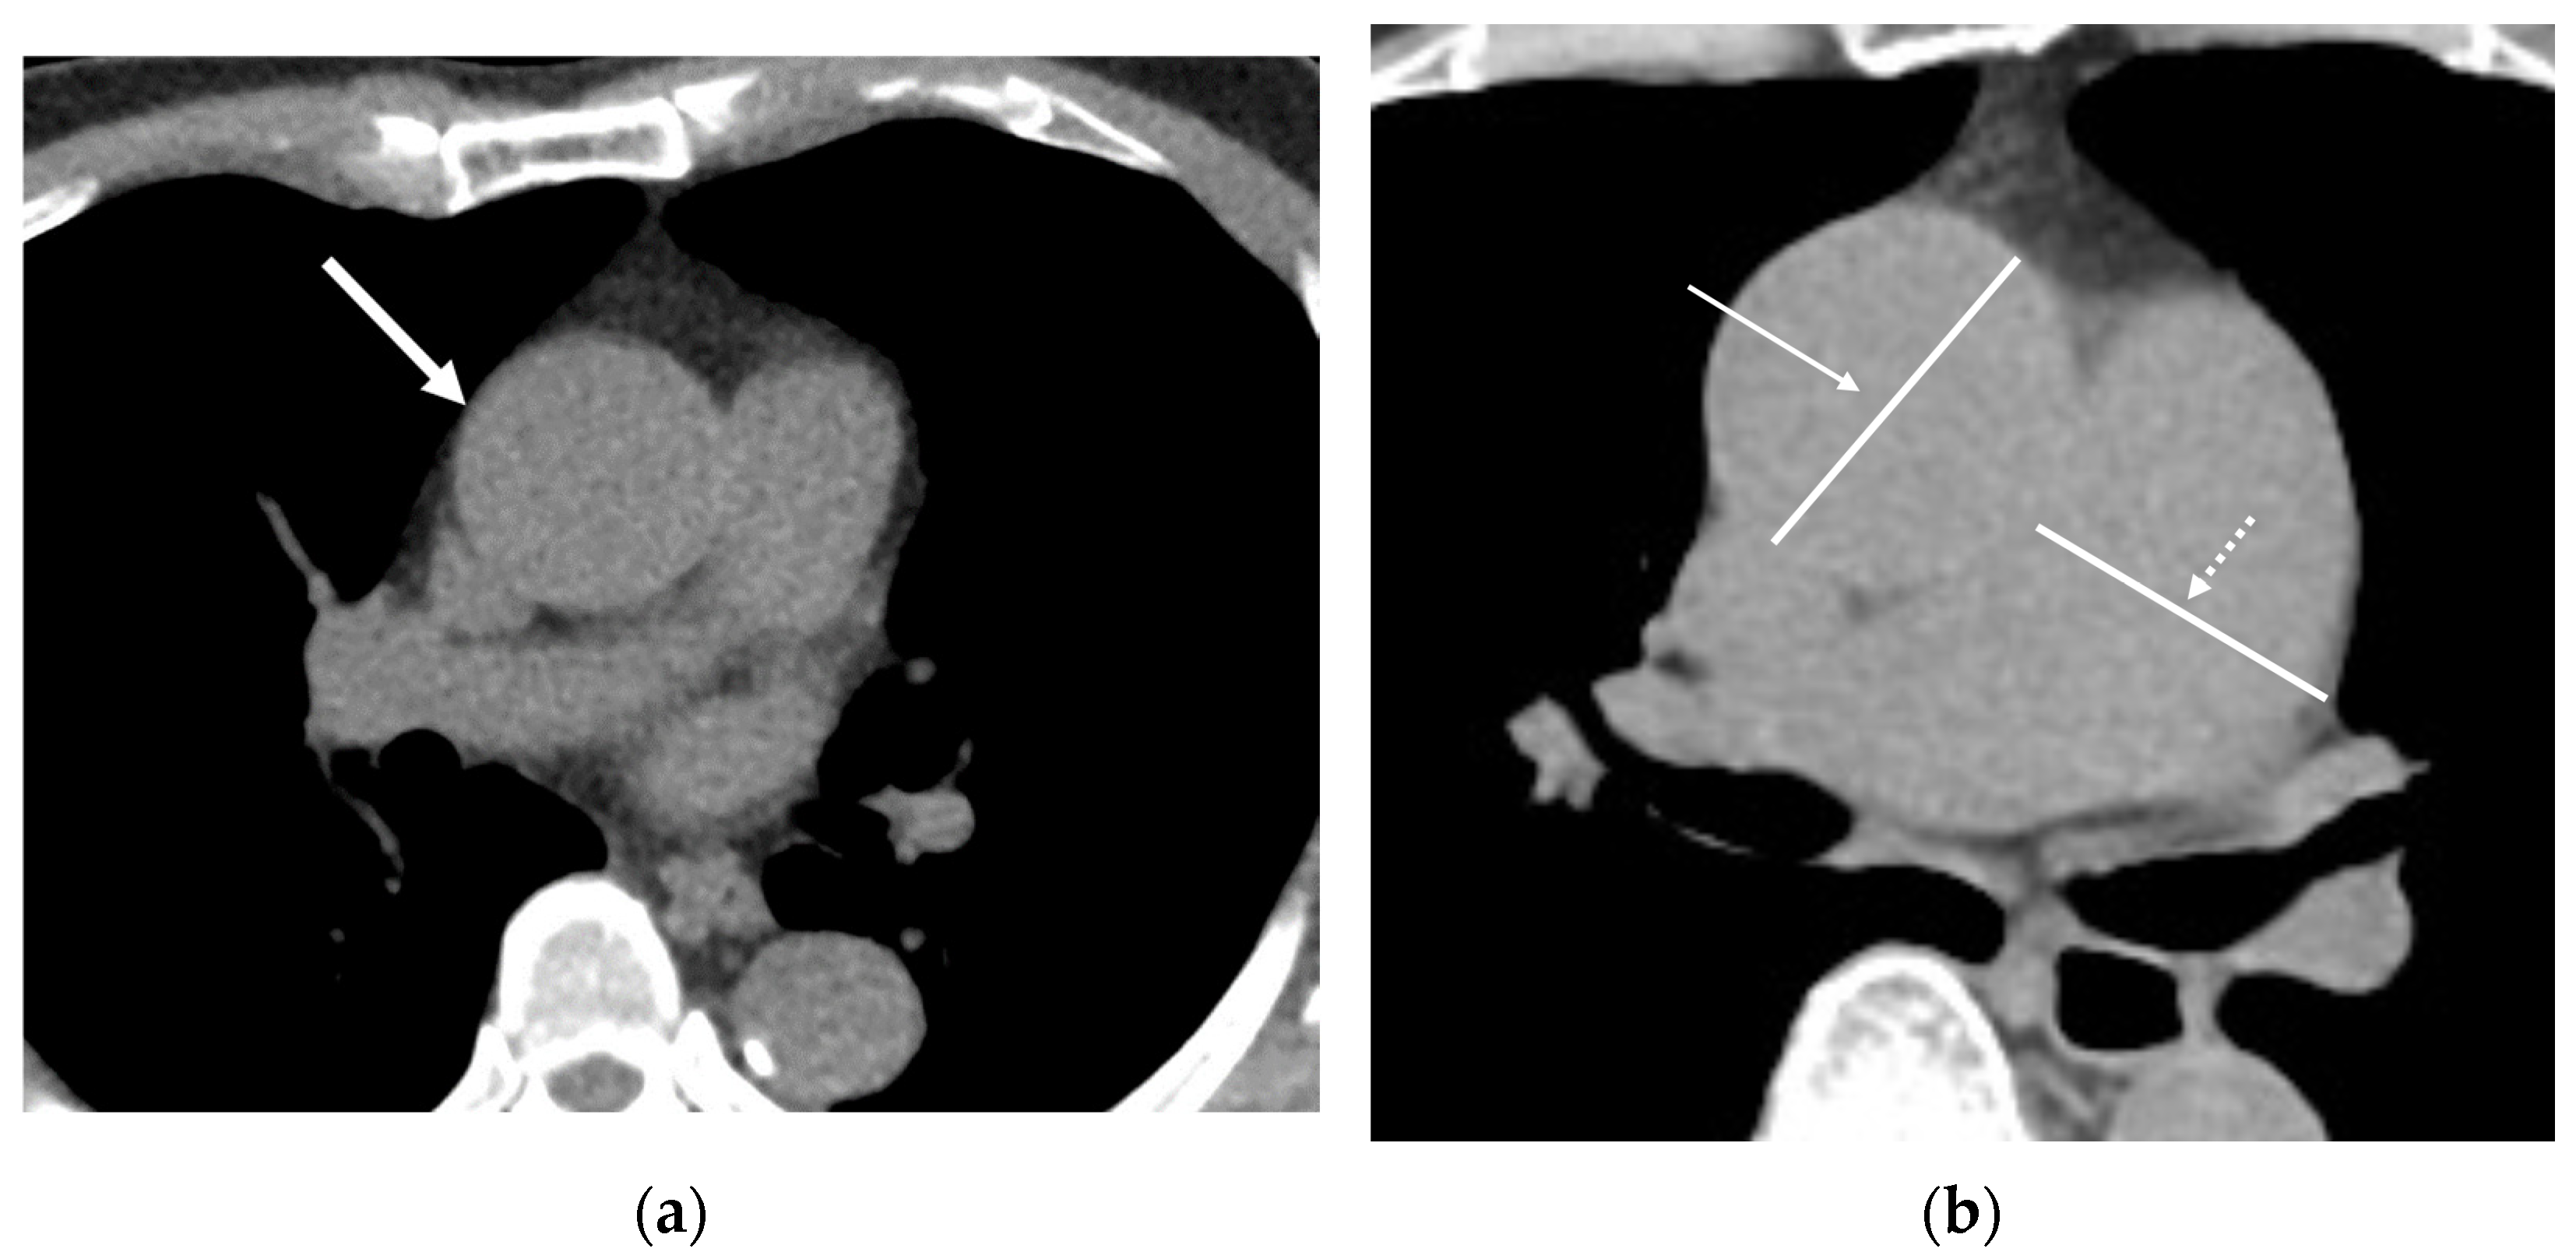

4.2. Aorta and Pulmonary Artery

4.3. Aortic Valve Calcification (AVC)